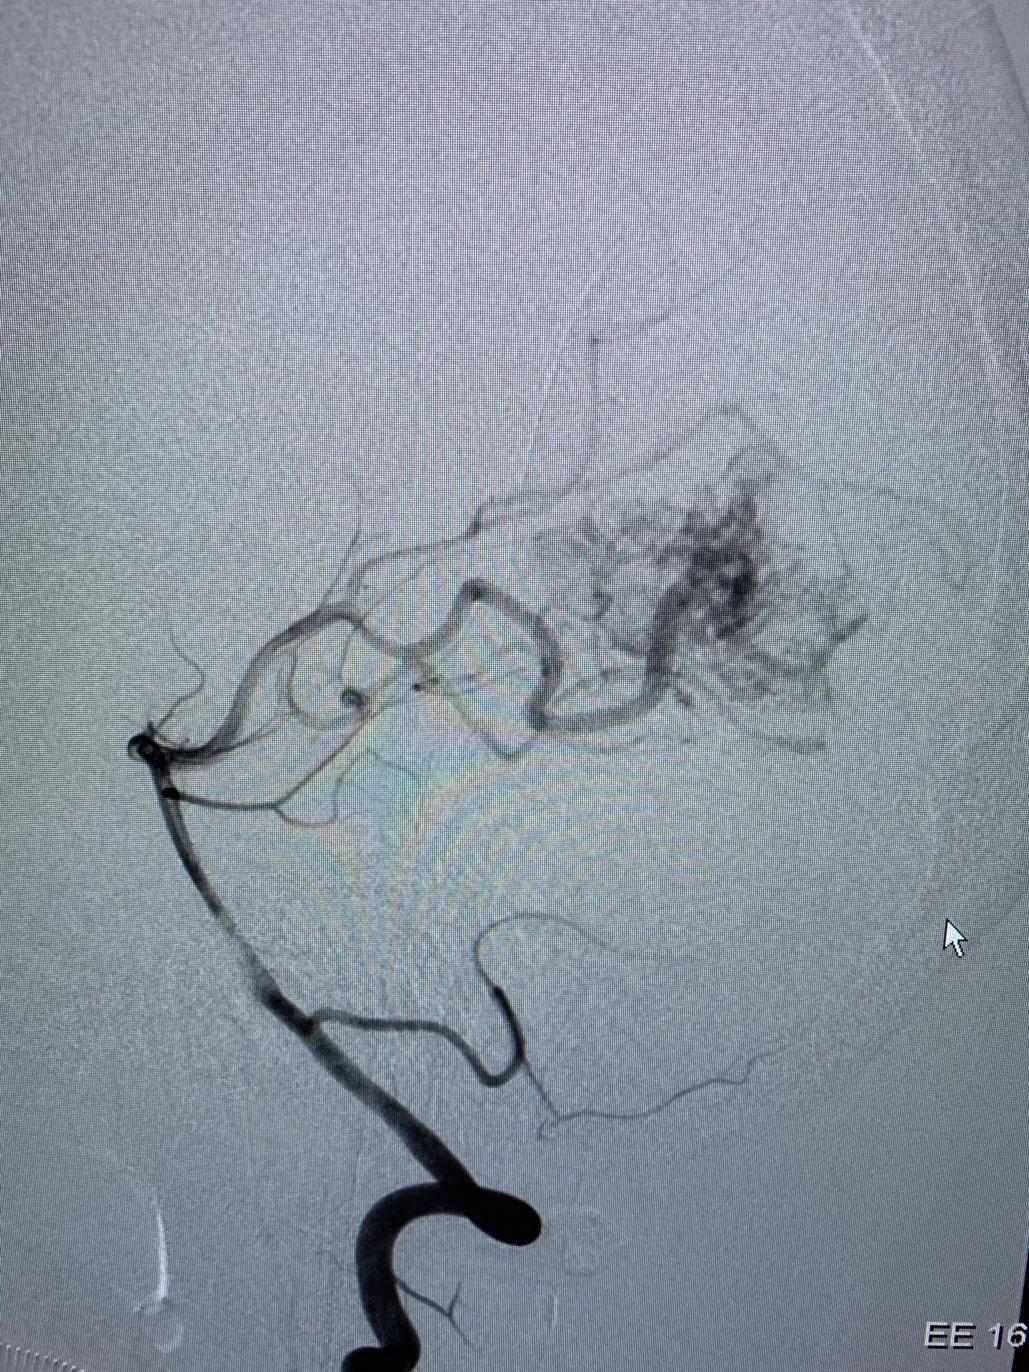

本组部分病例在使用Apollo微导管进行Onyx栓塞时,采用此种技术,可有效的阻止Onyx返流。本病例为一小女孩,右侧枕叶血管畸形,主要供血动脉为右侧大脑后动脉。